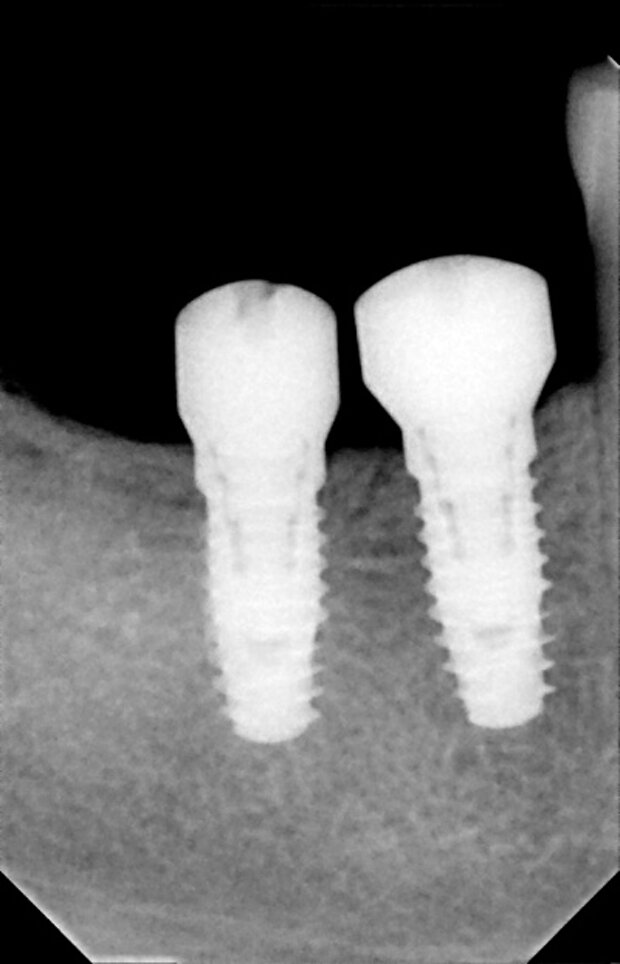

L'implantologia è la branca dell'odontoiatria che mira alla sostituzione di un dente naturale andato perduto mediante l'inserimento di una vite implantare in titanio che ne riproduce la radice senza che vengano coinvolti i denti vicini.